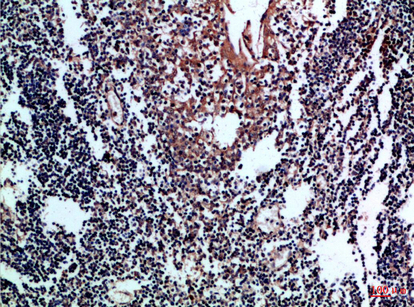

CD80 Polyclonal Antibody

| IHC-P, IF, ICC, E |

| Dilution | IHC-P~~IHC-p 1:50-200, ELISA 1:10000-20000 IF~~1:50~200 ICC~~N/A E~~N/A |